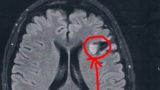

ガンガン、ズッキーンズッキーンて感じで左側の開頭したほうが相当痛い。

びまん性星細胞腫グレード2を患ってます。